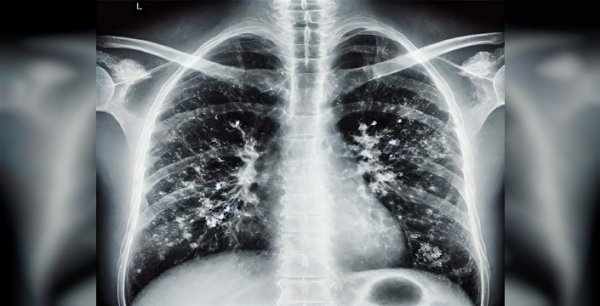

Prof. dr. Şener'den süperenfeksiyon alarmı: Aşı olmadan tehlike kapıda!

Prof. Dr. Alper Şener, gribal enfeksiyon sonrası süperenfeksiyon riskine dikkat çekerek ücretsiz grip aşısı ve zatürre aşısı olmayı tavsiye ediyor, özellikle yaşlıları uyarıyor.